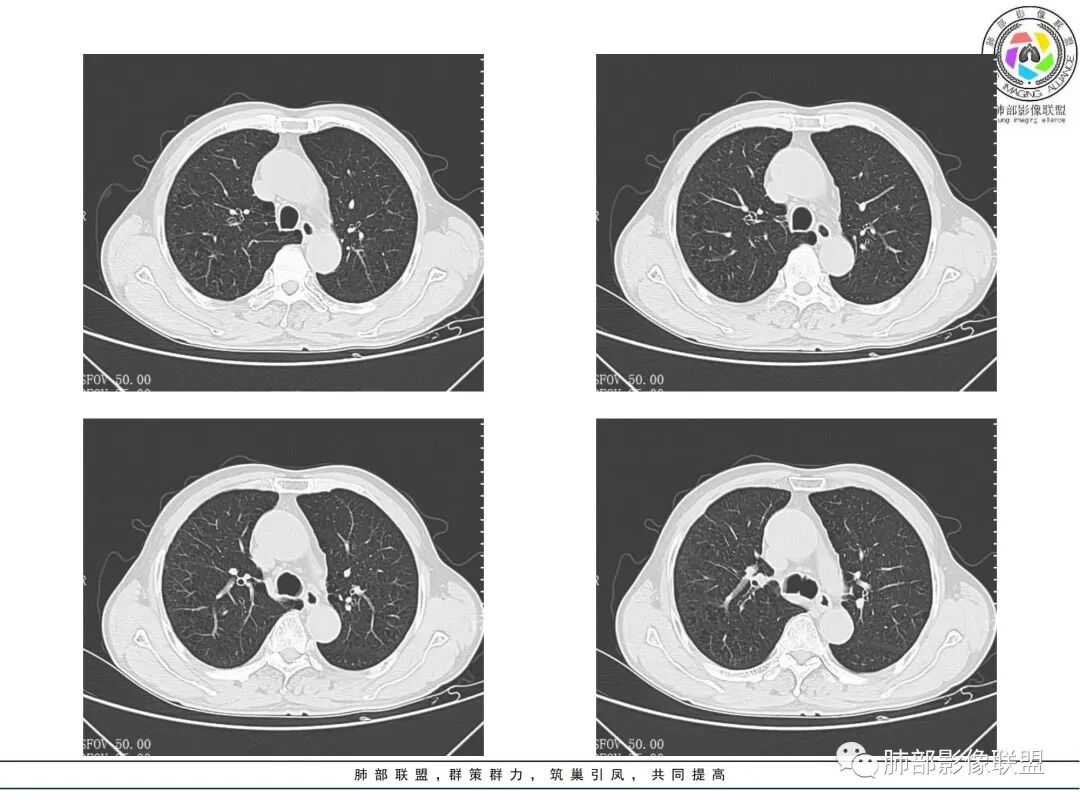

男,70,反复乏力、纳差20天,发热1天。胸部CT:肺气肿背景,右肺上叶中叶大团片影,实变十磨玻璃渗出。增强实性斑片影内密度不均,可见多发低密度坏死及不规则空洞影,空洞内壁尚光滑,血管边缘模糊。支气管管壁增厚,管腔通畅。右下叶可见小片渗出影。考虑支气管肺炎进展?病原考虑能形成肉芽肿、坏死空洞的微生物,TB?奴卡?鉴别鳞癌。

老年男性,乏力纳差,进食量明显下降,发热,后期少许黄脓痰,无咯血。无胸痛。未提口腔卫生情况,发热时间段不明确,肺气肿背景,气管内痰拴还是其他?觉得是外朝内进展病灶,右肺多叶段病灶,支气管通畅,支气管壁弥漫增厚,实变病灶内有坏死,坏死边界比较清晰,血管破坏不明显,周围散在磨玻璃,边界模糊,无树芽,实变内可疑小钙化,右侧胸水,肺门纵隔淋巴结无明显肿大。病史不太支持化脓菌感染,真菌里隐球强化不太支持,结核需要排除,厌氧菌感染带排,冠状位矢状位病灶觉得类圆形,临床肿瘤也是不能轻易排除的

发热,炎性指标高。右肺上叶实变影,凝固型坏死,裂隙状空洞,有钙化,有间质结节,考虑感染性病变,TB可能,鉴别肺炎性肺癌。

两个病灶独立,又有关联性,内侧病灶近端的支气管包绕在外侧病灶之中,但是走形自然

无堵塞迹象,支气管壁弥漫增厚

内部大片坏死区,其中还有不规则空洞

坏死腔内壁清,有强化环

肺动脉在实变区走形自然,坏死腔周围受压推移,走形自然,坏死区内破坏

这类坏死区内空洞,提示坏死液比较粘稠

不是液化坏死,液化坏死,这么大,有气体进来按理会形成液气平面

凝固性坏死